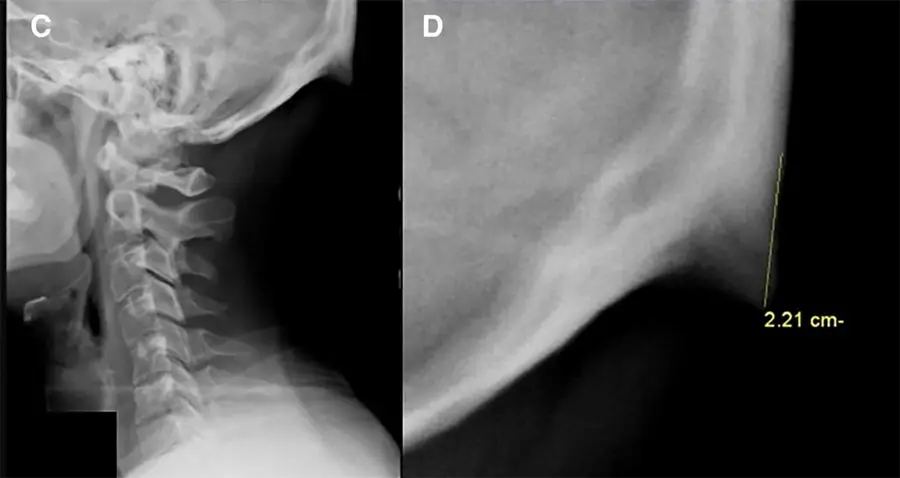

A los humanos nos está saliendo una espina justo encima del cuello y los teléfonos celulares tienen la culpaSociedad25/06/2023